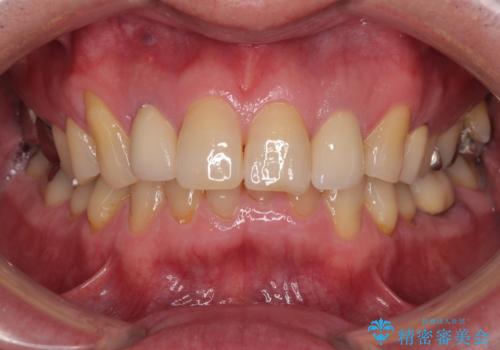

見た目、機能面共に満足していただけました。

右上2番目の歯の違和感もなくなったと喜んでいただけました。

今後もメンテナンスで通ってもらいながら、治療が必要になってきたところは順次行っていく予定です。